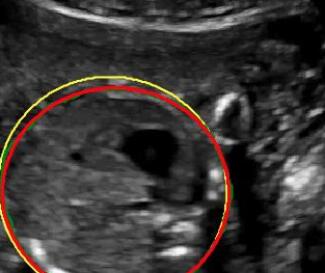

We propose a novel method based on convolutional neural networks (CNNs) to automatically estimate pixel-wise confidence maps of acoustic shadows in 2D US images. Our method learns an initial latent space of shadow regions from images consisting of multiple anatomies and with global image-level labels (“has shadow” and “shadow-free”), e.g. Fig. 1(a). The basic latent space is then estimated by learning from fewer images of a single anatomy (fetal brain) with coarse pixel-wise shadow annotations (approximately of the images with global image-level labels), e.g. Fig. 1(b). The resulting latent space is then refined by learning shadow intensity distributions using fetal brain images so that the latent space is suitable for confidence estimation of shadow regions. By using shadow intensity information, our method can detect more shadow regions than the coarse manual segmentation, especially relatively weak shadow regions.

We propose a shadow-seg module to extract generalized shadow features for a large range of shadow types in fetal US images under limited weak manual annotations. Since shadow regions have different shapes, various intensity distributions and uncertain edges, the pixel-wise annotation of shadow regions is time consuming and relies heavily on annotator’s experience (e.g. various annotations in Fig. 1(b)). This generally results in manual annotations of limited quantity and quality. Compared with pixel-wise shadow annotations, global image-level labels (“has shadow” and “shadow-free” in our case) are easier to obtain, and shadow images with global image-level labels can contain a larger variety of shadow types. Therefore, we use a shadow-seg module that combines unreliable pixel-wise annotations and global image-level labels as weak annotations.The proposed shadow-seg module contains two tasks, (1) shadow/shadow-free classification using image-level labels, and (2) shadow segmentation that uses few coarse pixel-wise manual annotations ( of the global image-level labels). Shadow features can be extracted during simple shadow/shadow-free classification and subsequently optimized for the more challenging shadow segmentation task. In our case, shadow features extracted by the classification network cover various shadow types in a range of anatomical structures. These shadow features become suitable for the shadow segmentation after being optimized by a shadow segmentation network.

This data set comprises 643 fetal brain images and has no overlap with the multi-class data set. Shadow regions in this data set have been coarsely segmented by two bio-engineering students using trapezoid-shaped segmentation masks for individual shadow regions.